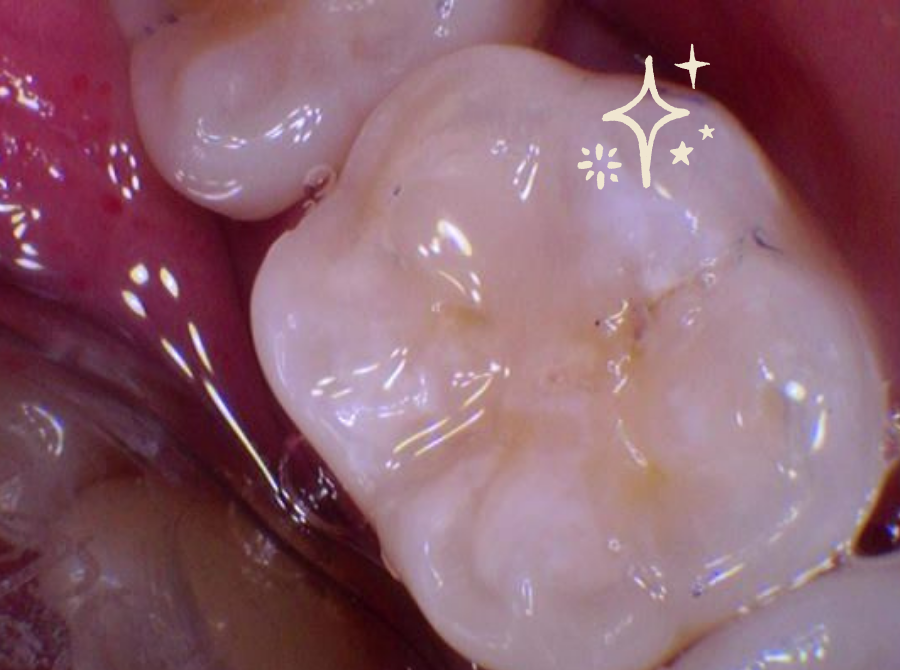

4. Application of the Filling

High-quality composite resin is placed in layers, shaped carefully, and set with a specialised light.

We routinely use a rubber dam to keep the tooth dry, enhance adhesion, and improve long-term success.

5. Shaping & Final Checks

Once the filling is hardened, we refine its shape, check your bite, and ensure the restored tooth looks and feels just right.

The result is a natural-looking, functional tooth that supports your long-term oral health.